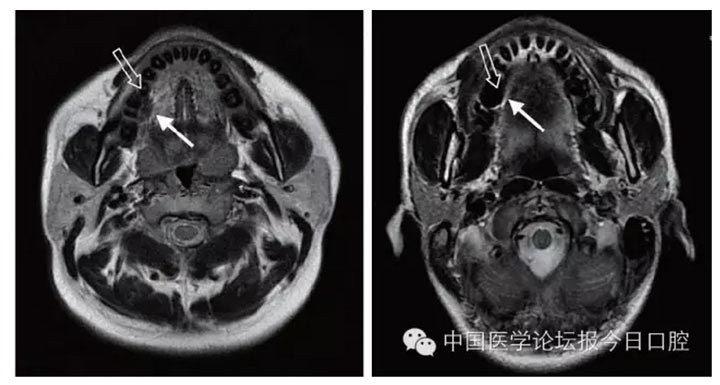

在MRI 檢查中,金屬產(chǎn)生偽影的大小與金屬材料的磁化率及磁場(chǎng)強(qiáng)度相關(guān),磁化率越大、磁場(chǎng)強(qiáng)度越高,產(chǎn)生的偽影越大。偽影不僅使金屬所在處局部解剖結(jié)構(gòu)變形或消失,還會(huì)沿頻率編碼方向擴(kuò)散到遠(yuǎn)處,嚴(yán)重影響被檢查部位及鄰近組織觀察

文獻(xiàn)研究中常使用的金屬包括鎳鉻合金、鈷鉻合金、低鈦合金、純鈦、金合金、金鈀合金、銀鈀合金等成分如表所示。大量研究得出近乎一致性的結(jié)論。金合金、金鈀合金、銀鈀合金對(duì)MRI影響甚微,與全瓷材料、丙烯酸樹(shù)脂極為相似,表現(xiàn)為修復(fù)體影像邊緣光滑、無(wú)變形、無(wú)偽影;純鈦金屬對(duì)MRI影響較小,接近于全瓷材料;但有的研究卻發(fā)現(xiàn)純鈦在核磁共振場(chǎng)中也產(chǎn)生偽影,但偽影涉及的掃描層數(shù)較少;低鈦合金(鈦合金)對(duì)MRI影響較大,介于純鈦和鎳鉻合金之間,中度偽影;鎳鉻合金、鈷鉻合金對(duì)MRI影響很大,鈷鉻合金更甚;表現(xiàn)為重度偽影、圖像扭曲變形(圖1、圖2)。不難看出,對(duì)MRI 影響,全瓷材料、樹(shù)脂材料<金合金等貴金屬<純鈦<低鈦合金<鎳鉻合金<鈷鉻合金。有研究發(fā)現(xiàn)鈷鉻合金橋偽影大小與修復(fù)體長(zhǎng)軸一致,影響范圍為固定橋近遠(yuǎn)中徑2倍,頰舌徑的4倍;相同外形金屬修復(fù)體厚度增加,偽影增加。單個(gè)金屬樁核偽影可波及到上頜竇、牙槽骨、舌體、舌下腺等組織器官,但對(duì)眼底、眼內(nèi)容物、腦組織和頸椎成像基本無(wú)影響。